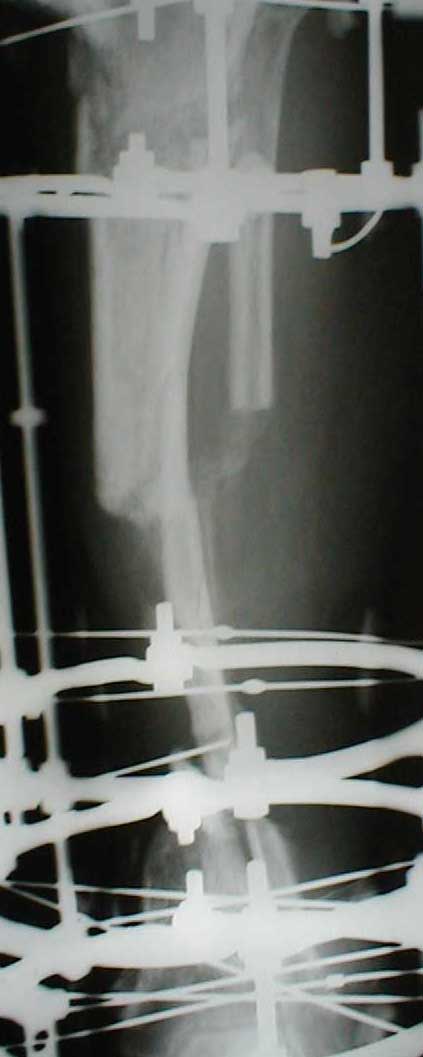

В приложении - моё наблюдение (возможно, уже представлял, тогда

извините).

Нога попала в пресс.

Ко мне больной попал черз 1,5-2 года после травмы и нескольких

операций с синегнойной инфекцией на всю голень. Меня пригласили на консультацию

насчет ампутации.

Лечил я его месяцев 8.

Малоберцовка полностью перестроилась, нога опороспособна.

При ходьбе на дальние расстояния пользуется тростью.

Осталась трофическая язва, периодически закрывается.